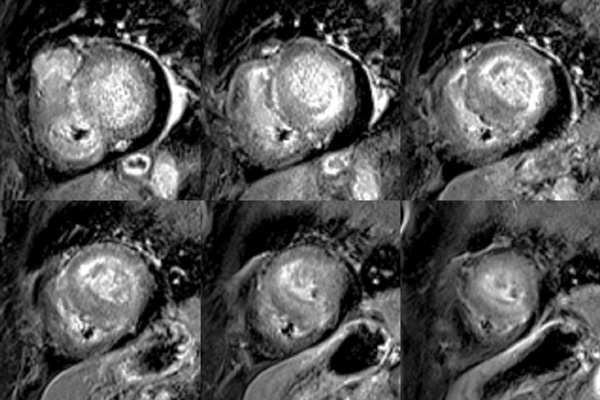

Figure 1A : Séquence Ciné-IRM - Coupes petit-axe basal

Figure 1B : Séquence Ciné-IRM - Coupes petit-axe médian

Figure 1C : Séquence Ciné-IRM - Coupes petit-axe apical

Figure 1D : Séquence Ciné-IRM - Coupes 2-cavités

Figure 1E : Séquence Ciné-IRM - Coupes 3-cavités

Figure 1F : Séquence Ciné-IRM - Coupes 4-cavités

- Présence d’une hypertrophie ventriculaire gauche (HVG) asymétrique à prédominance septale mesurée au maximum à 23 mm.

- Visualisation de la sonde de PM avec artéfacts métalliques modérés au niveau du ventricule droit (flèches roses).

- Présence d’un épanchement péricardique de moyenne abondance (flèches rouges).